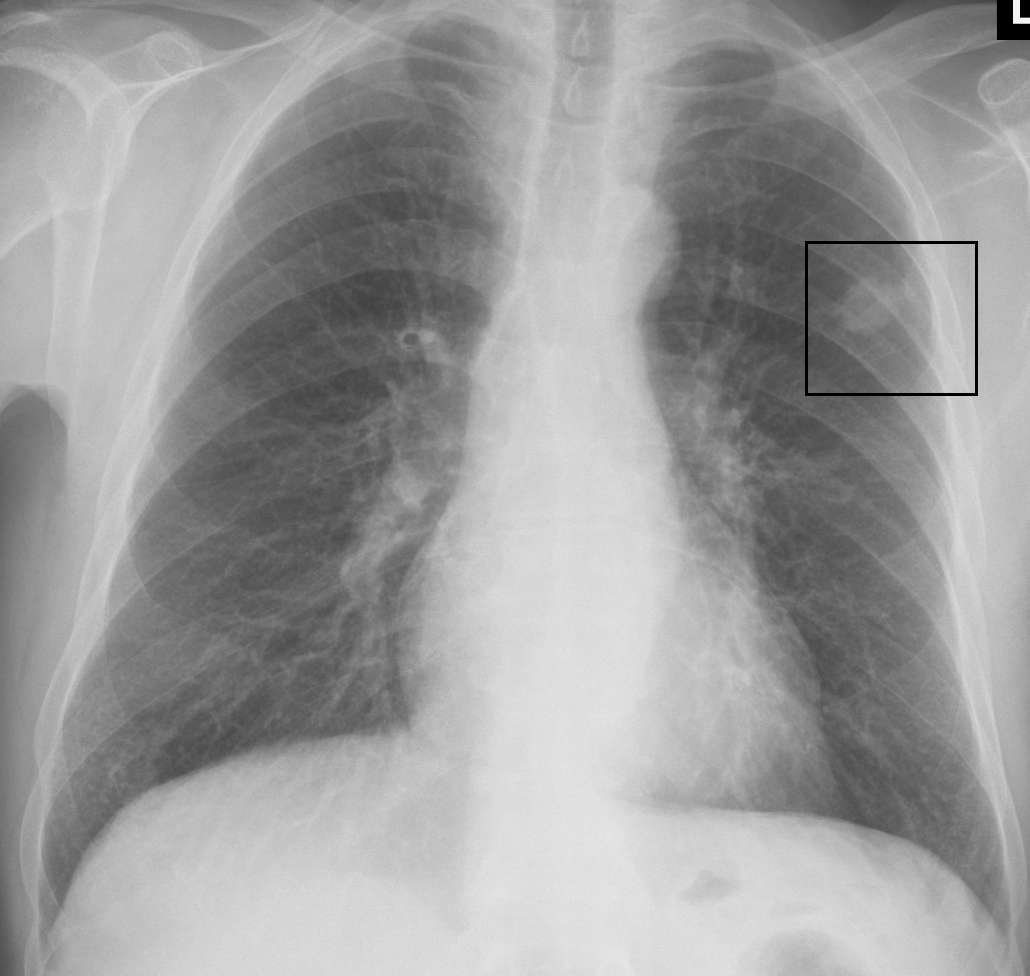

암의 진단은 징후나 증상이 나타나거나 검진을 통해 이루어진다.[120] 하지만 확정적인 진단을 위해서는 병리학자가 조직 샘플을 검사해야 한다.[121] 암이 의심되는 사람들은 혈액 검사, X선, (조영증강) CT 스캔, 내시경 검사 등 의학 검사를 받는다.

검진 방법으로는 X선 촬영, 초음파 검사, 컴퓨터 단층 촬영(CT), 자기 공명 영상(MRI), 양전자 방출 단층 촬영(PET), 골 신티그래피[322], 소화기 내시경 검사[323]가 있다.

검진 방법으로는 X선 촬영, 초음파 검사, 컴퓨터 단층 촬영(CT), 자기 공명 영상(MRI), 양전자 방출 단층 촬영(PET), 골 신티그래피[322], 소화기 내시경 검사[323] 등이 있다.